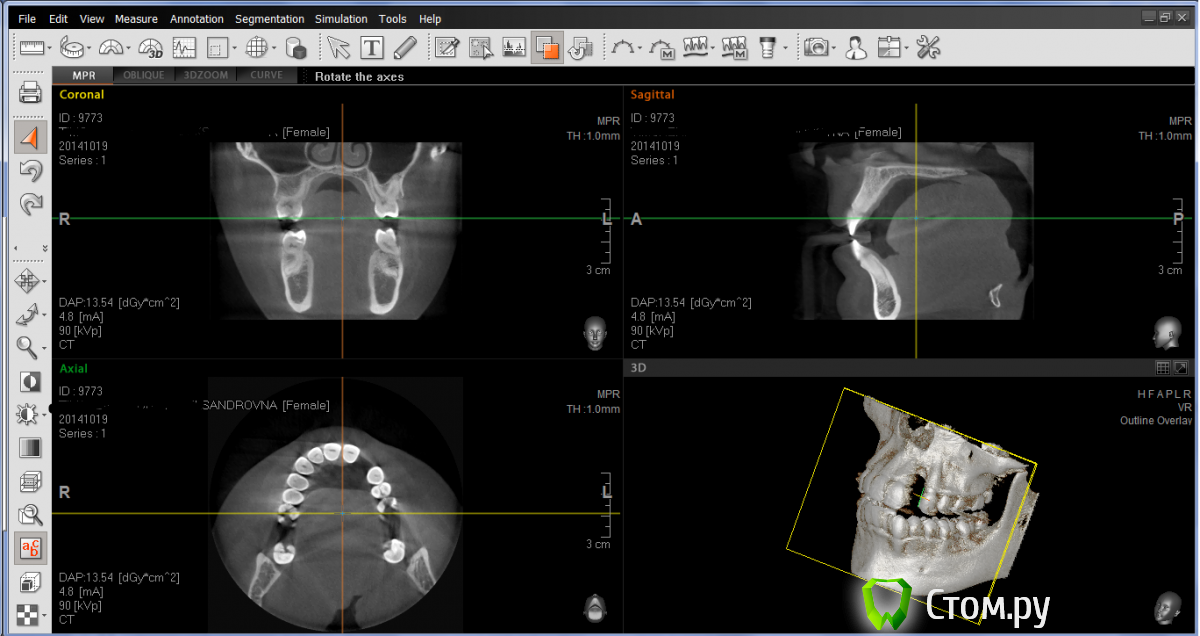

LuBoF Опубликовано 24 октября, 2014 Автор Поделиться Опубликовано 24 октября, 2014 Вот еще попытка. Ссылка на комментарий

Bier Опубликовано 24 октября, 2014 Поделиться Опубликовано 24 октября, 2014 ваш врач прав. Хотите имплантат - придется зуб этот удалять. Либо мягкие ткани туда подсаживать и делать мост 2 Ссылка на комментарий

LuBoF Опубликовано 24 октября, 2014 Автор Поделиться Опубликовано 24 октября, 2014 А на место переднего зуба придется тоже кость наращивать для импланта? Ссылка на комментарий

Bier Опубликовано 25 октября, 2014 Поделиться Опубликовано 25 октября, 2014 Там одной операцией все нарастят 1 Ссылка на комментарий